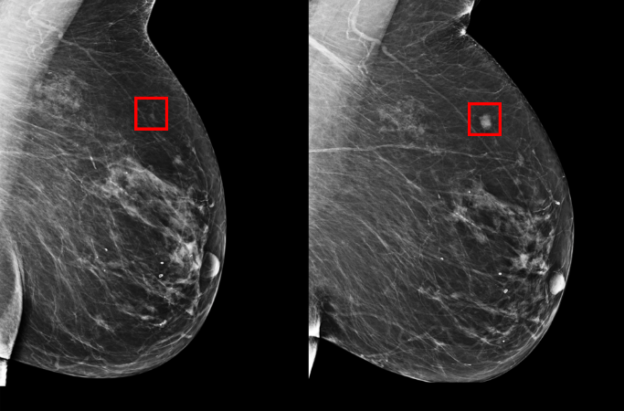

據瞭解,這款深度學習模型接受了超過 9 萬張乳房 X 光照片的訓練,也因此能在 X 光照片中辨識出人類醫生無法辨識出的微小圖案,以目前來說,能夠辨識出 31% 在未來 5 年發展為乳腺癌風險最高的患者。雖然比例聽起來並不高,但與現行醫生可用的任何模型相比(早期階段只能辨識出 18%),結果明顯要好上許多。

儘管系統在實用前還需進行廣泛驗證,但深度學習模型可以透過訓練辨認出乳房 X 光照片數據中的模式,而人類靠肉眼並無法做到,隨著訓練數據越大,模型辨認的結果也將更加準確,可想見未來在預測應用上將更為廣泛◆